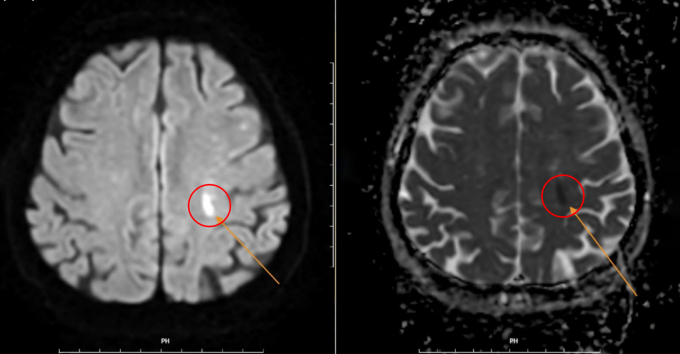

Để tránh bỏ lỡ thời gian điều trị lý tưởng, êkíp kích hoạt quy trình Code stroke (cấp cứu đột quỵ) để chụp CT và MRI cho kết quả sớm nhằm khẳng định chẩn đoán. Kết quả chụp MRI cho thấy nhồi máu, phù hợp với biểu hiện yếu liệt nửa người bên phải (yếu liệt xảy ra bên nào thì vị trí nhồi máu não ở bên ngược lại).

Chụp MRI xác định chính xác tình trạng nhồi máu não. Ảnh: Phòng khám Đa khoa Tâm Anh Quận 7